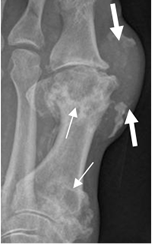

Fig 134. Artropatía por gota.

Rx AP del pie. Lesiones radiolúcidas, de bordes escleróticos, en el 1º metatarsiano (Flechas delgadas), con prominencia de tejidos blandos, que corresponde a tofo. (Flechas gruesas).